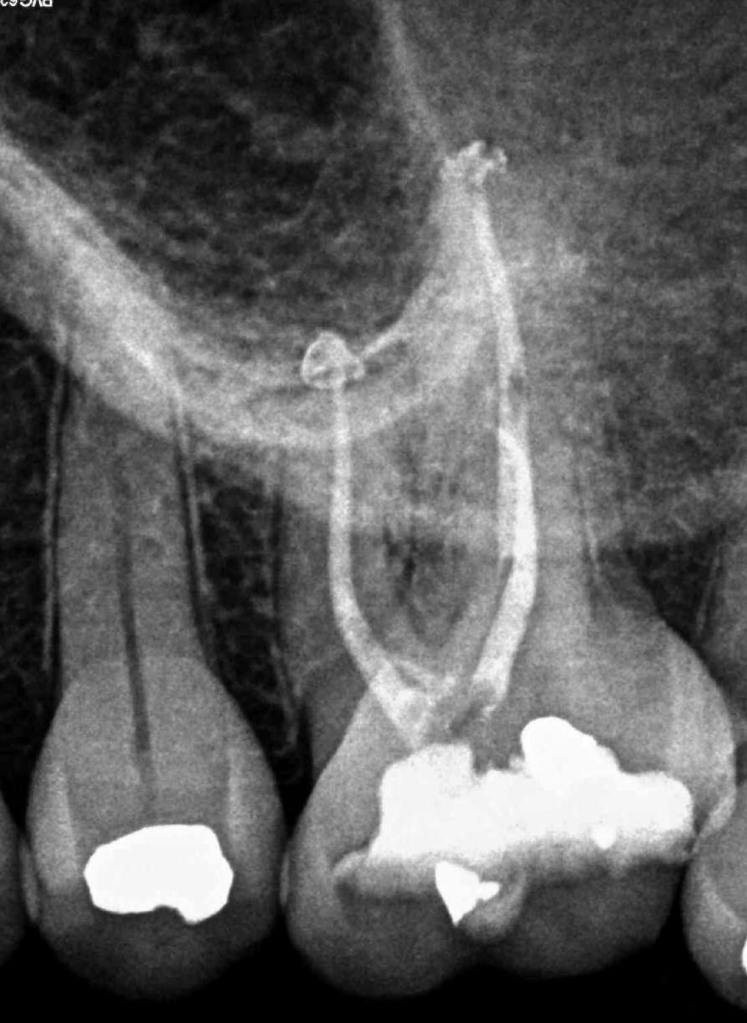

CALCIFICADOS

Premolar calcificado lesion

Premolar superior conducto platino sin tratar